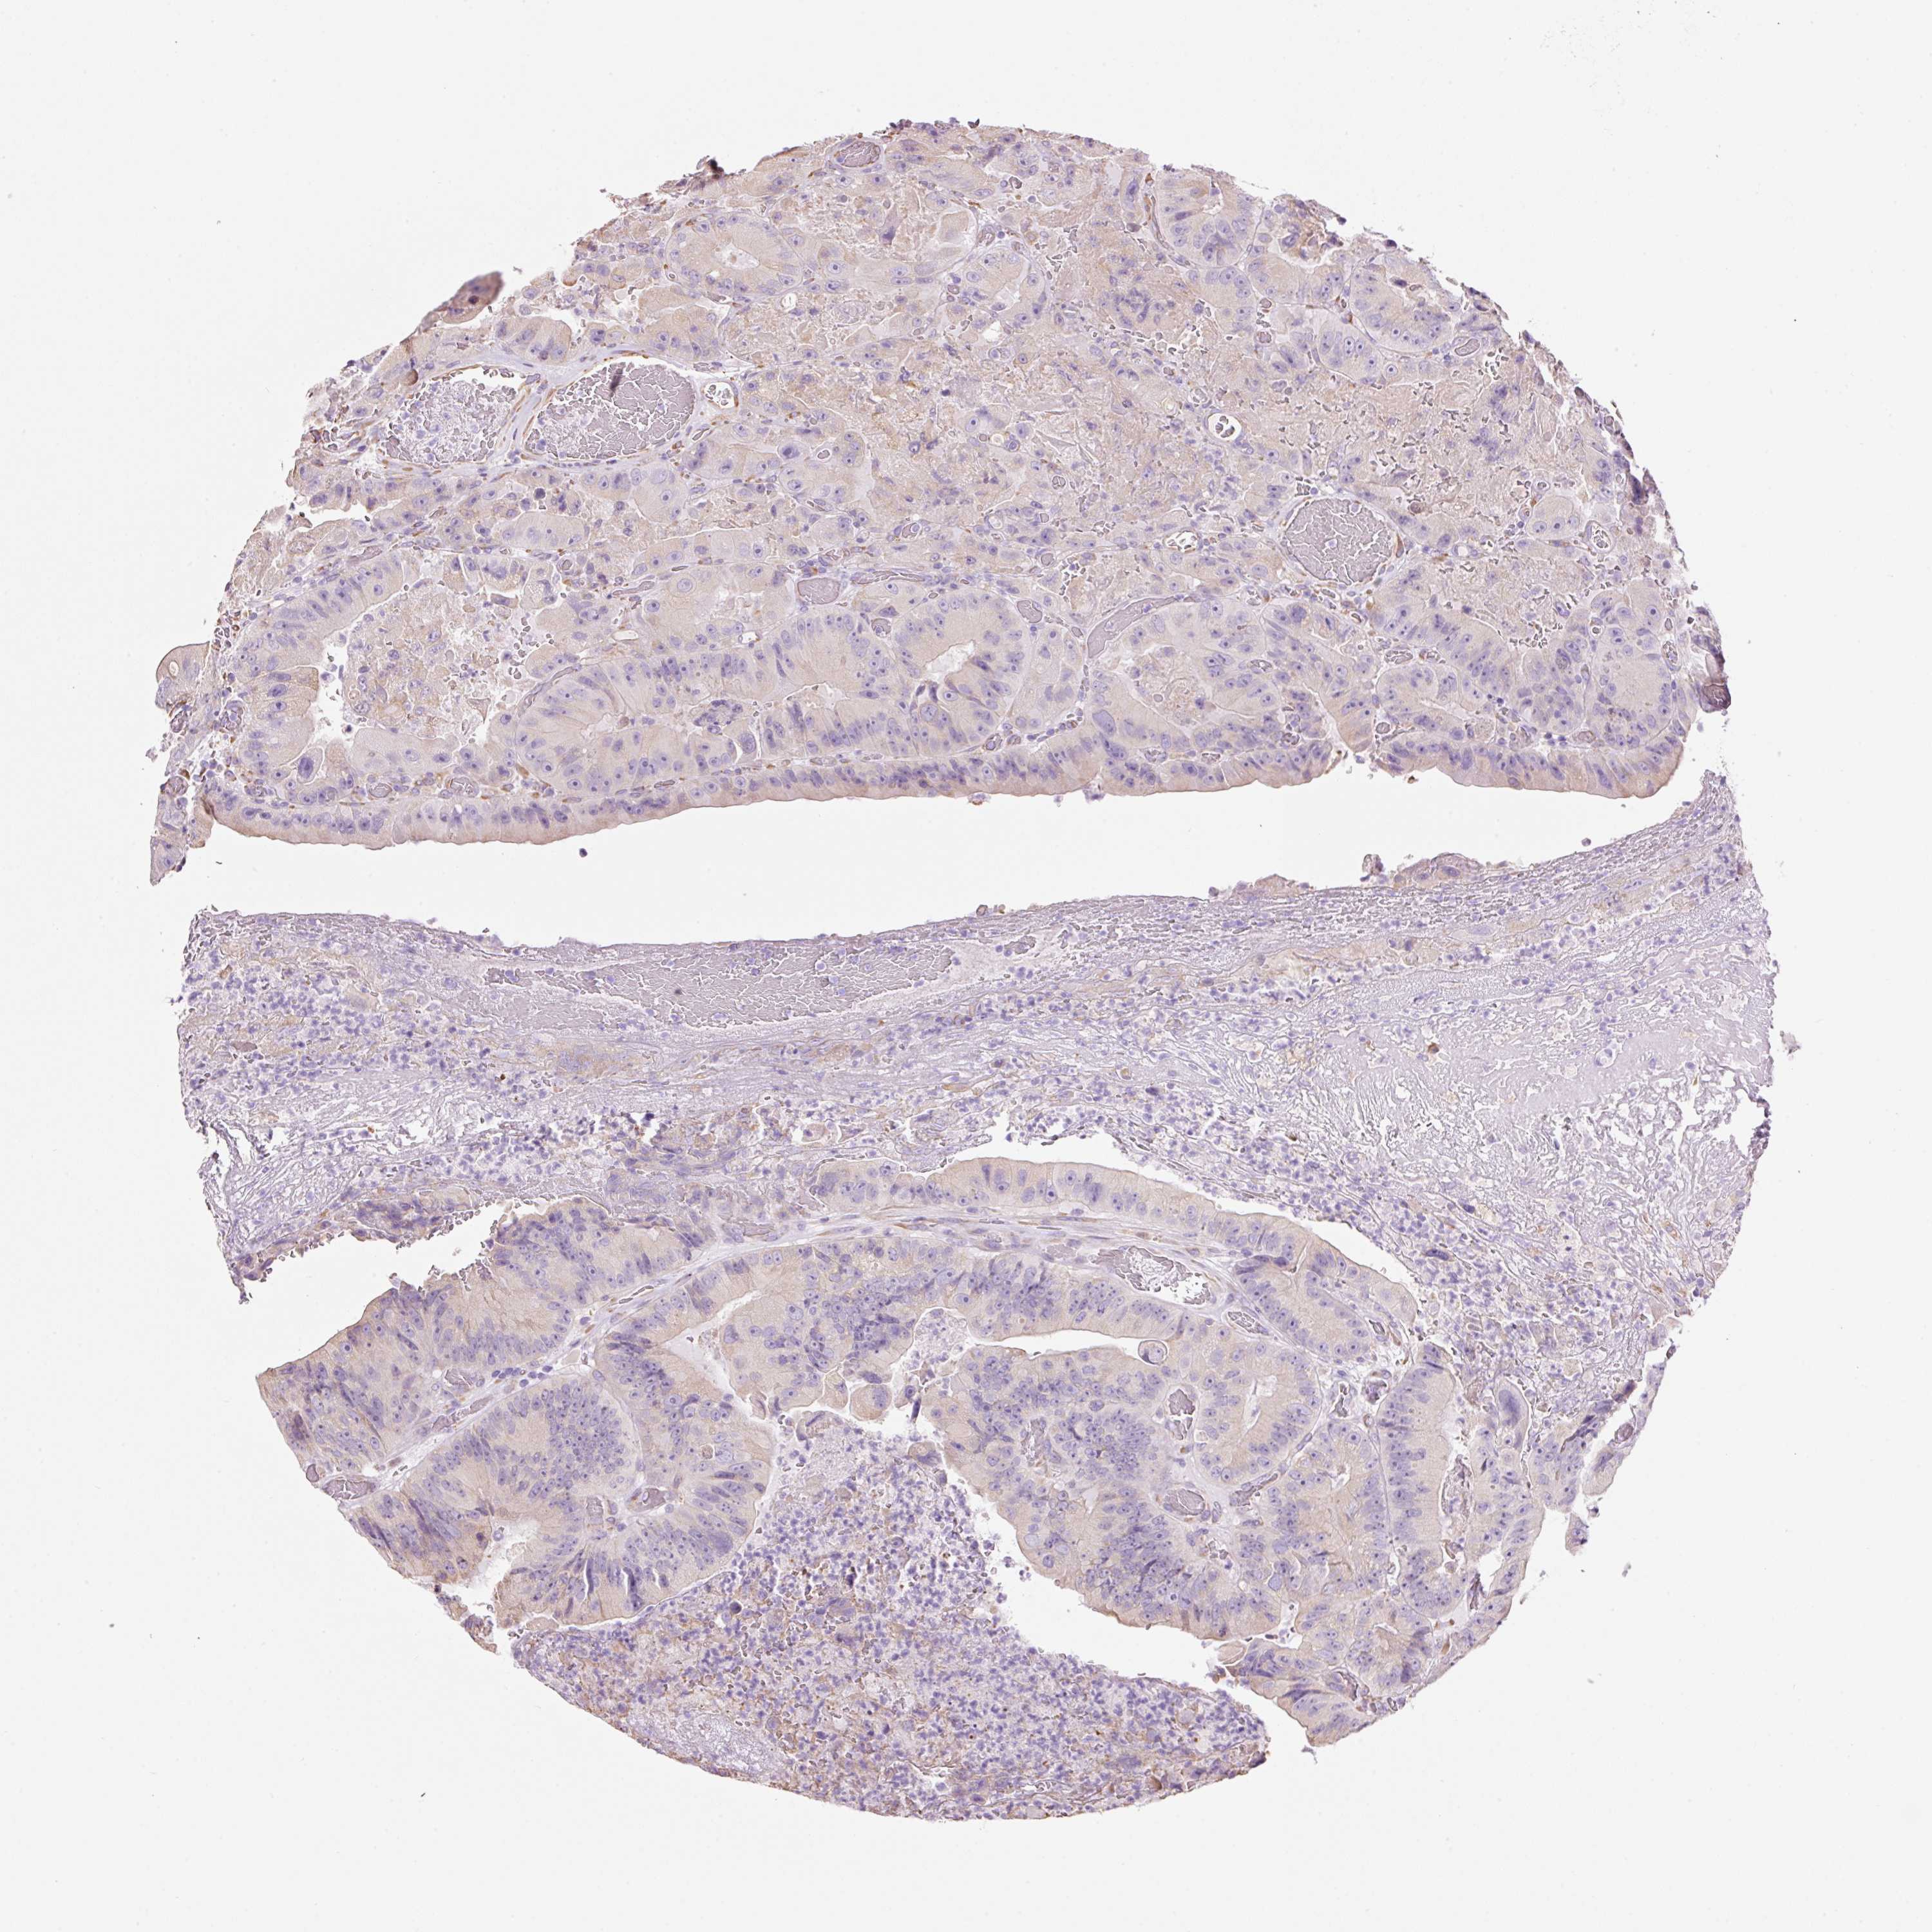

Colorectal cancer

Human cancer

Colon adenocarcinoma